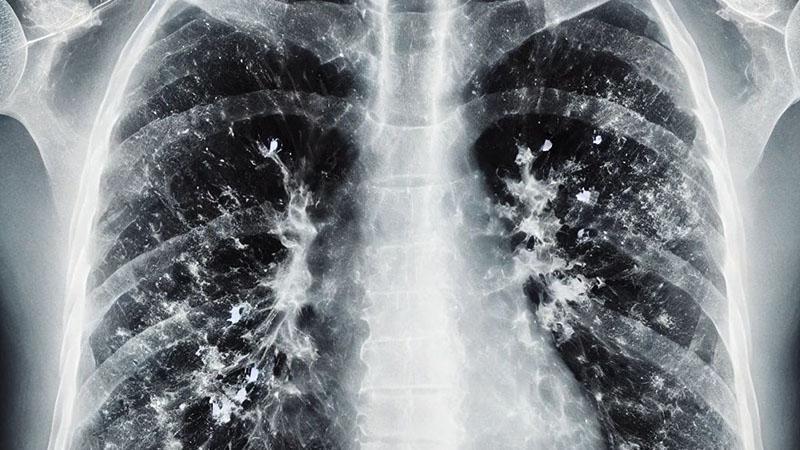

Göğüs Hastalıkları Uzmanı Prof. Dr. Tevfik Özlü, solunum yolu enfeksiyonlarının en sık görüldüğü kış aylarında, zatürre hastalığının grip ya da soğuk algınlığıyla karıştırılabileceğini ancak bazı kritik belirtilerin ayırt edici olduğunu belirterek, uyarılarda bulundu. Özlü, "Şu sıralar pek çok hasta zatürreyi fark edemiyor ve teşhiste geç kalıyor. Oysa zatürrede erken tanı çok önemli. Hekimin, 4 saat içinde doğru tedaviye başlaması, zatürreye bağlı ölümleri anlamlı şekilde azaltıyor" dedi.

Zatürrenin grip ya da soğuk algınlığıyla karıştırılabileceğini belirten Prof. Dr. Özlü, "Bu tür enfeksiyonlar genelde üst solunum yollarında yerleşir. Oradan başlar ve nezle, soğuk algınlığı, farenjit, sinüzit gibi üst solunum yolu enfeksiyonlarına yol açar. Bazen de alt solunum yollarına ilerleyerek bronşit, bronşiolit gibi hafif hastalıklara yol açabilir. Fakat zatürre, bu hastalıklar arasında en ağır olanıdır. Maalesef, şu sıralar pek çok hasta zatürreyi fark edemiyor ve teşhiste geç kalıyor. Oysa zatürrede erken tanı çok önemli. Hekimin, 4 saat içinde doğru tedaviye başlaması, zatürreye bağlı ölümleri anlamlı şekilde azaltıyor" ifadelerini kullandı.

Zatürre tanısında en önemli belirtilerin nefes darlığı ve öksürük olduğunu ifade eden Özlü, "Şikayetleriniz tedaviyle ya da tedavisiz olarak ilk birkaç gün içinde azaldıktan sonra tekrar ikinci bir atak yaşanıyorsa; ateşlenme ve şikayetlerde artış oluyorsa bu da zatürrenin eklendiğini gösterebilir. Nefes darlığı çok önemli bir belirti. Özellikle nefes alıp vermekte zorlanıyorsanız, özellikle bebeklerde ve yaşlılarda solunum sayısının dakikada 24'ün üzerine çıkması, nefes alıp verirken hırıltı olması, bebeklerde burun kanatlarının solunuma eşlik etmesi, nabız sayısının dakikada 120'nin üzerine çıkması gibi durumlar zatürre olasılığını güçlendirir. Öksürük de önemli bir belirti. Zatürrede öksürük genellikle yaş öksürüktür. Yani balgamlıdır. Balgamın koyu renkli olması; kahverengi, koyu sarı, koyu yeşil gibi ve kıvamlı olması zatürre ihtimalini artırır. Ateşin çok yüksek olmasıyla birlikte yan ağrısı dediğimiz, öksürürken ya da nefes alırken batıcı şekilde hissedilen bir yan ağrısı varsa, bu da zatürreye işaret edebilir" dedi.